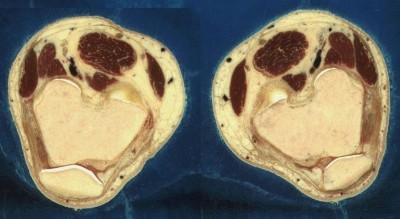

Грудь.

Дело в том, что криосекция (cryosection), как сообщает словарь, — это «изготовление срезов из замороженных тканей или клеток». Иными словами, для получения требуемых изображений человеческое тело замораживается и тонко-тонко нарезается, наподобие салями. Имена людей, трупы которых шинковали исследователи из «Наглядного человека», понятное дело, не разглашаются; известно только, что это были 39-летний убийца с электрического стула и 59-летняя женщина, умершая от инфаркта. Трупы были заморожены до 85 градусов ниже нуля и, как выражаются отдельные русские эммигранты, послайсены на ломти толщиной в 1 (мужчина) и 1/3 (женщина) мм. Каждый срез аккуратно фотографировался; в результате получился 1871 снимок мужика и немного больше 5000 — тетки.